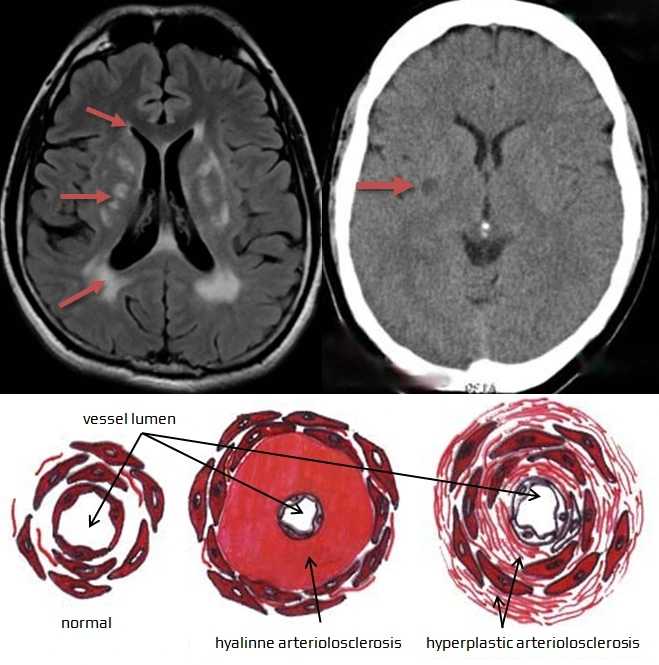

혈관성 치매는 뇌의 작은 혈관들이 막혀 발생하는 열공성 뇌경색으로 인해 생깁니다. 이는 일반적인 뇌졸중과는 다른 특징을 가지고 있습니다:

## 열공성 뇌경색의 특징

- 뇌의 아주 작은 혈관들이 막힘

- 큰 뇌졸중과 달리 한쪽 마비 등의 뚜렷한 증상이 없을 수 있음

- CT 촬영 시 뇌에 작은 구멍들이 뚫린 것처럼 보임

## 혈관성 치매의 진행

1. 미세 혈관 폐색: 뇌의 작은 혈관들이 서서히 막힘

2. 뇌 조직 손상: 혈류 공급 부족으로 뇌 조직이 손상됨

3. 인지 기능 저하: 누적된 손상으로 전반적인 뇌 기능이 저하됨

## 진단 방법

- CT나 MRI 촬영: 뇌 내부에 작은 구멍들이 관찰됨

- 이는 시간이 지난 뇌경색의 흔적을 나타냄

혈관성 치매는 서서히 진행되며, 초기에는 증상이 뚜렷하지 않을 수 있습니다. 따라서 정기적인 건강검진과 혈관 건강 관리가 중요합니다.

뇌에 생기는 작은 구멍, 즉 열공성 뇌경색은 겉으로 보기에는 작지만 매우 위험할 수 있는 뇌 손상입니다.

- 뇌의 아주 작은 혈관들이 막혀서 발생

- 직경 1-15mm 정도의 작은 구멍 형태로 나타남

- CT나 MRI 촬영 시 뇌에 구멍이 뚫린 것처럼 보임

- 주로 기저핵, 뇌간, 대뇌 백질 등 뇌 깊은 부위에서 발생

## 위험성

- 증상이 없어 '침묵성 뇌경색'이라고도 불리지만 실제로는 매우 위험

- 인지 기능 저하와 운동 기능 장애 위험 증가

- 향후 뇌졸중과 치매 발병 위험 상승

- 65세 이상 노인의 25-30%에서 발견될 정도로 흔함

## 원인과 예방

- 고혈압이 가장 중요한 위험 요인

- 혈압 관리, 금연, 규칙적인 운동 등 혈관 건강 관리가 중요

- 항혈소판제 치료가 도움될 수 있으나 출혈 위험도 고려 필요

열공성 뇌경색은 작지만 뇌 건강에 큰 위협이 될 수 있습니다. 정기적인 건강검진과 혈관 건강 관리를 통해 예방하는 것이 중요합니다.